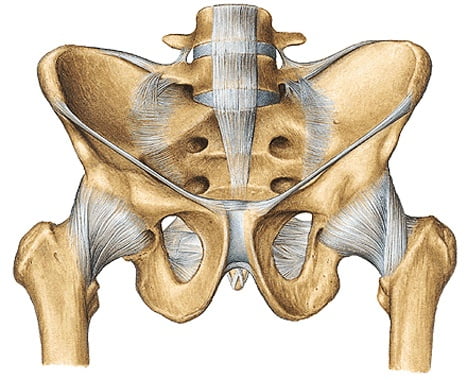

Дегенеративно-дистрофические изменения в тазобедренном суставе лежат в основе заболевания, называемого коксартрозом. Представители старшего поколения, возраст которых превышает пятьдесят лет, автоматически попадают в группу риска. Это закономерное явление, обусловленное естественными анатомическими процессами, начинающих свое проявление с возрастом.

Распространенность заболевания тазобедренного сустава объясняется большими нагрузками, которые испытывает самый крупный сустав, задействованный при ходьбе, беге, прыжках. Женская половина населения чаще заболевает коксартрозом в виду физиологических особенностей, которым подвергается женский организм в течение жизни.

Болезнь характеризуется следующими видоизменениями:

- хрящевая ткань прекращает синтезироваться, рессорная функция утрачивается, хрящ становится тонкий и неэластичным;

- процесс активно распространяется на головку вертлужной кости, уплотняя и утолщая ее;

- суставная щель значительно уменьшается, образующиеся костные разрастания создают трение, вызывая боль при движении;

- внутренняя оболочка суставной капсулы раздражается и воспаляется;

- начинается незначительная деформация;

- больной старается разгрузить пораженную ногу, из-за чего происходит атрофия мышц бедра.